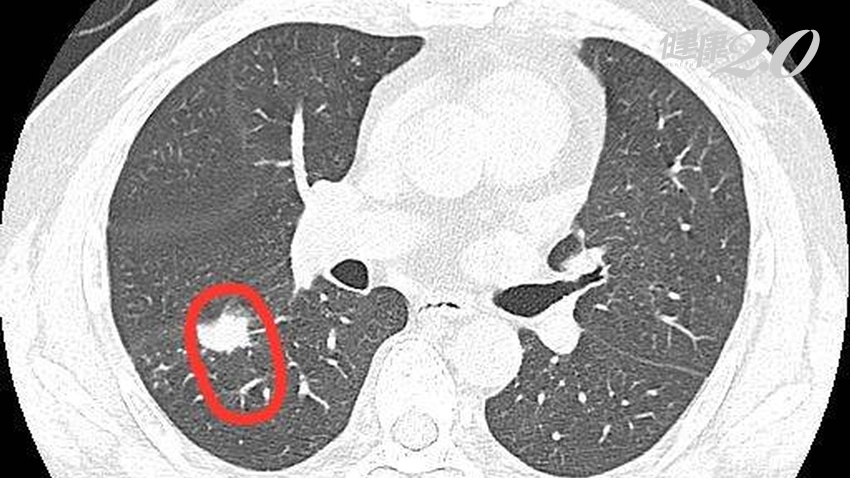

▲低劑量電腦斷層可以提高肺癌診斷的準確率。

近年發展出低劑量電腦斷層檢查,輻射劑量相當於15張傳統X光片,仍在每人每年輻射劑量安全標準內,確實可以提高診斷正確率以及診斷小於一公分的病灶達到及早治療的目的,但目前需要自費檢測,當影像判斷認為有問題的時候,需要進一步依靠病理切片檢查,如確定有惡性細胞才能診斷為肺癌。